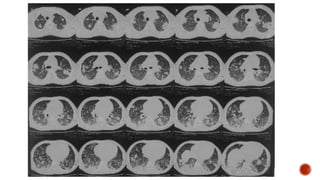

Frontal chest radiograph shows few ill defined patchy opacities in both the lung

fields, few of them showing cavitatory changes. TCC seen in situ.

Compared to the previous radiograph there is reduction in the number of opacities

with cavitatory changes.

 Malignancy:

 Squamous cell carcinoma of the lung

 Metastasis :

 squamous cell ca

 adenoca from GIT/breast

 sarcoma

 cervical carcinoma

 urothelial carcinoma of the bladder

 Infection :

 Septic embolism

 Pulmonary tuberculosis

 Abscess

 Post pneumonic pneumatocele

 Necrotizing pneumonia

 Autoimmune :

 Wegeners granulomatosis

 Rheumatoid nodules

 Distribution :

 Peripheral

 Lower lobe predominance

 Multiple

 Bilateral

 Varying stages of cavitation

 Feeding vessel sign